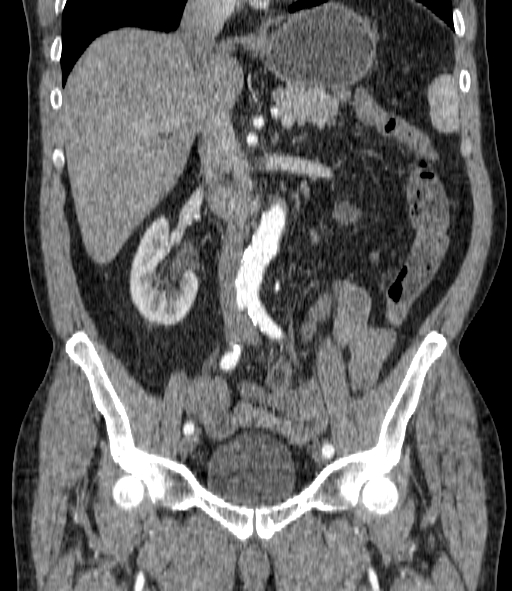

Уважаемые коллеги помогите определиться с изменениями в тонкой кишке. Пациент с жалобами на боли в левой подвздошной области.

Тип: Клиническое наблюдение

Область: Пищеварительная система

Модальность: КТ

Дата: 02.10.2015 - 14:57